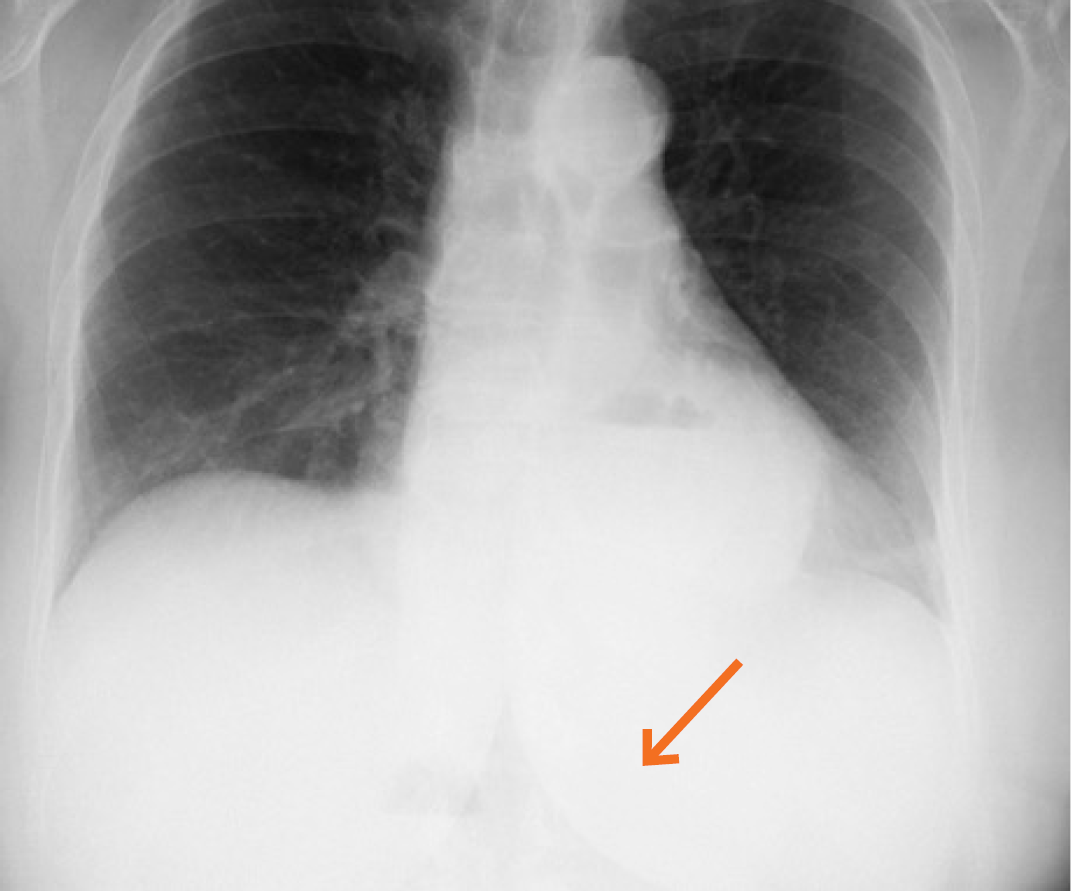

Figura 1 Radiografia de tórax: silhueta cardíaca com interposição da silhueta gástrica e evidência da câmara gasosa no tórax (seta).

A radiografia torácica mostrou hipotransparência sobreposta à silhueta cardíaca na base direita, com nível aéreo, sugestivo de hérnia do hiato, com câmara gástrica no hemitórax esquerdo (Fig. 1).